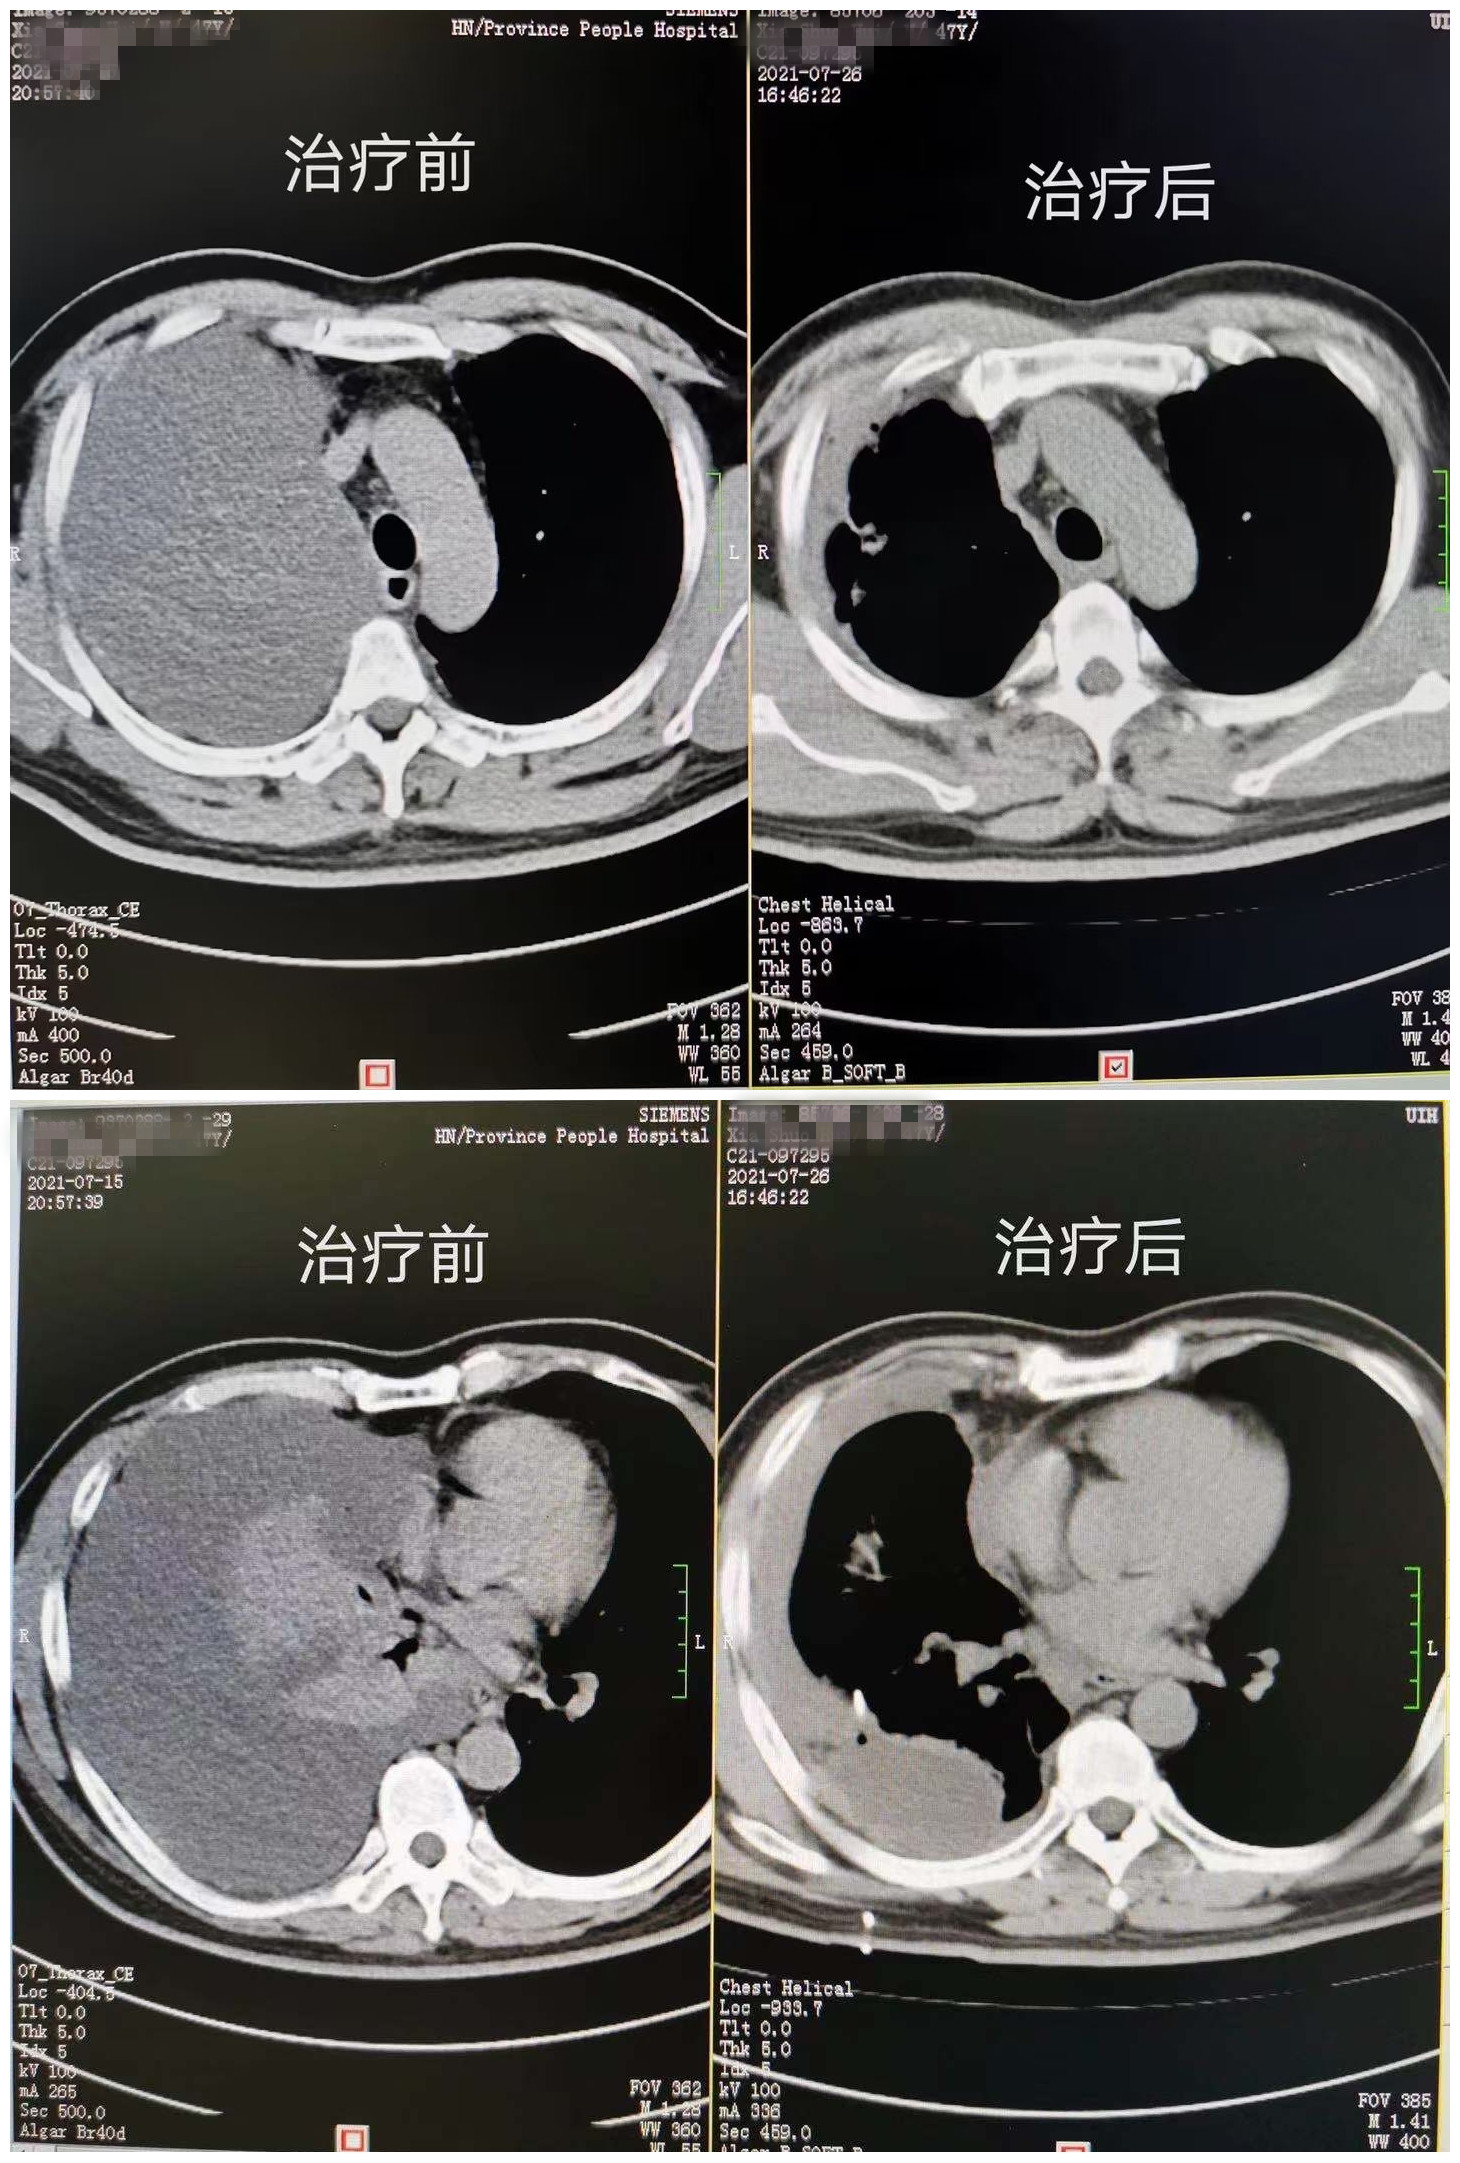

治疗前后CT对比

经过与患者和家属充分沟通,7月20日,刘念主任医师团队为夏先生进行了第一次胸腔热灌注治疗,术中患者生命体征平稳,无特殊不良反应,随后,夏先生顺利完成三次胸腔热灌注治疗,复查胸片及肺部CT提示胸水明显减少且胸膜粘连较满意,于7月26日出院,等候基因检测结果进行下一步综合治疗。